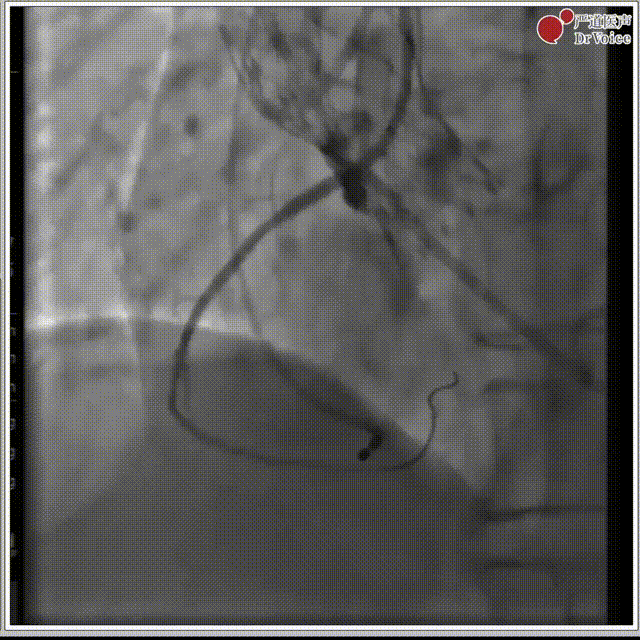

4. 植入23mm Evolut PRO瓣膜,过弓及瓣膜定位。

过弓,植入瓣膜

主动脉根部造影